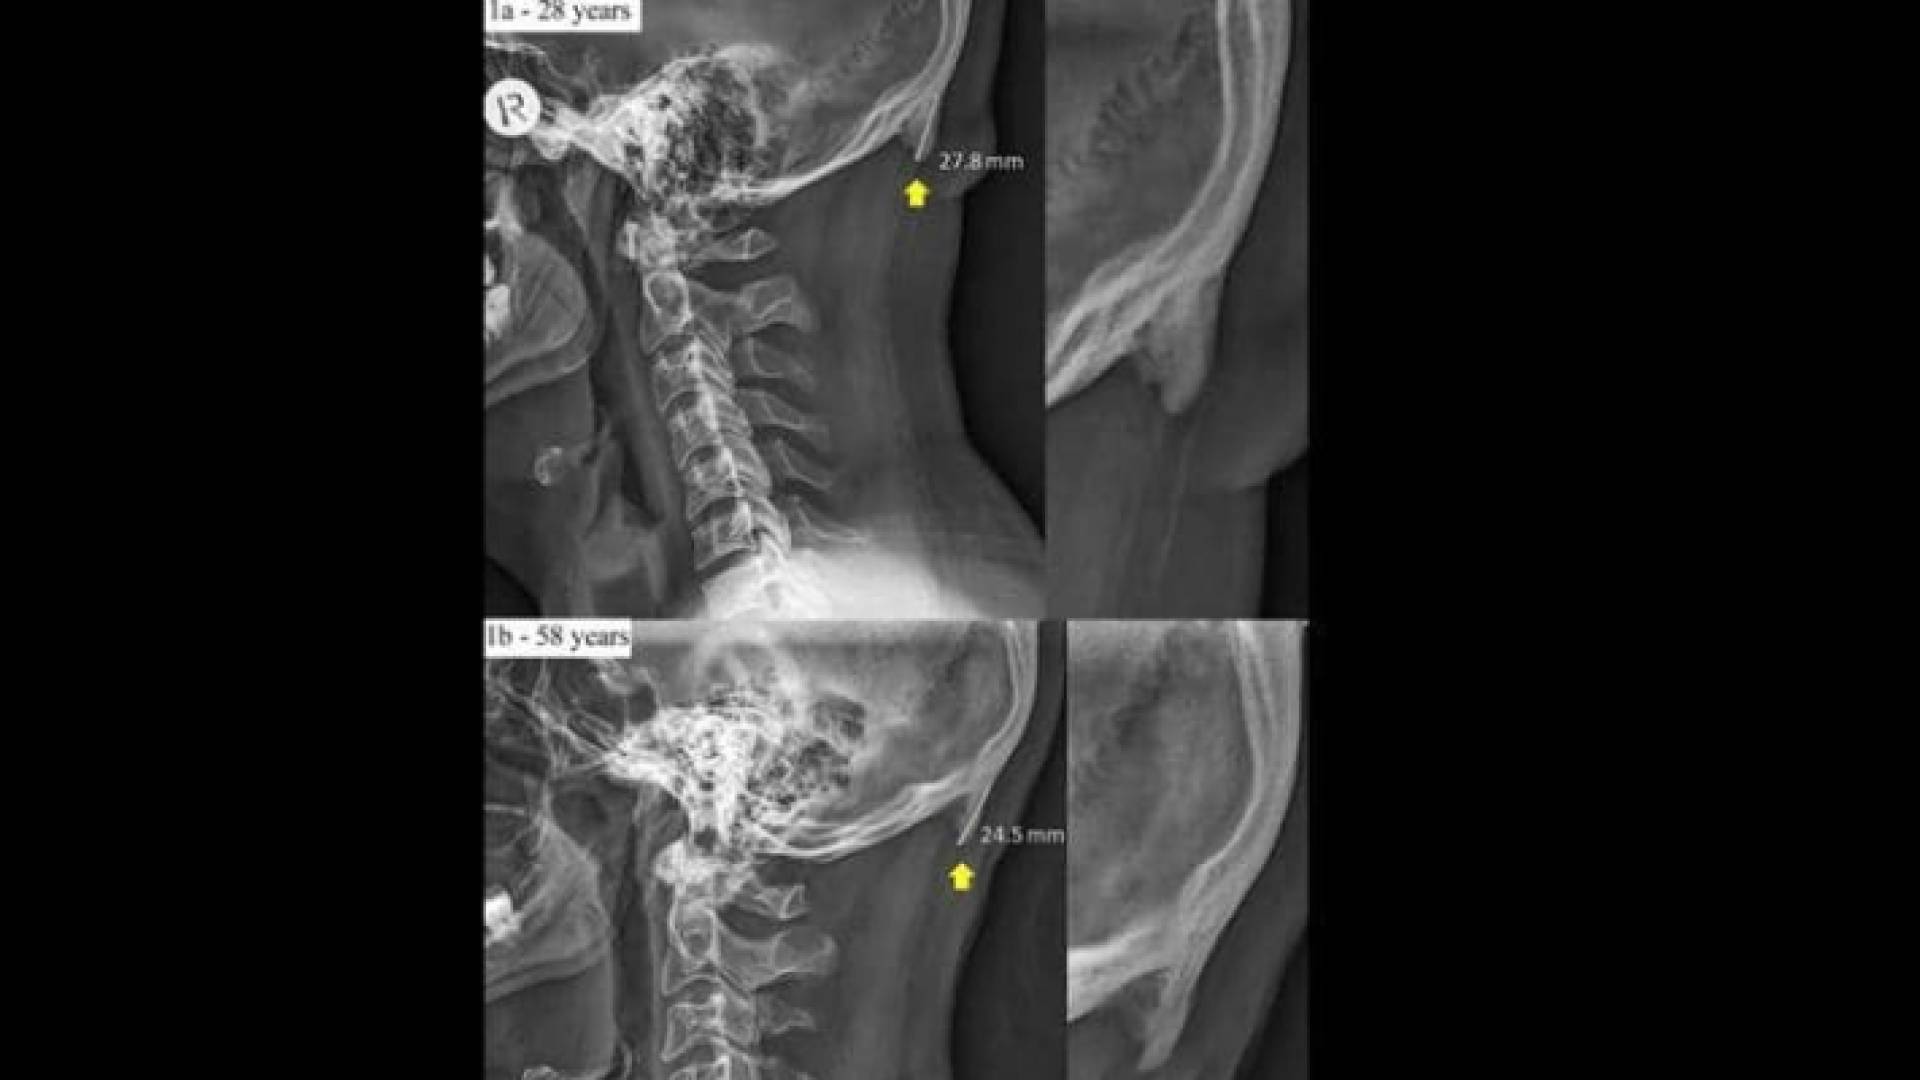

وقالت صحيفة "ديلي ميل" البريطانية وفق الدراسة إن الشخص الذي يكثر من استخدام الهاتف الذكي، يظهر لديه ما يشبه شوكة عظمية في الجهة الخلفية من جمجمة الرأس، بسبب الانحناء والتركيز في شاشة الجهاز.

وتوضح الدراسة التي جرى إعدادها في جامعة "سان شان كوست" الأسترالية، أن جمجمة الإنسان أضحت تحدث هذه "الشوكة العظمية" بشكل متزايد.

وتبرز هذه الشوكة العظمية بشكل أسرع لدى الشباب الذين تتراوح أعمارهم بين 18 و30 سنة، واعتمدت الدراسة على عينة من ألف جمجمة.